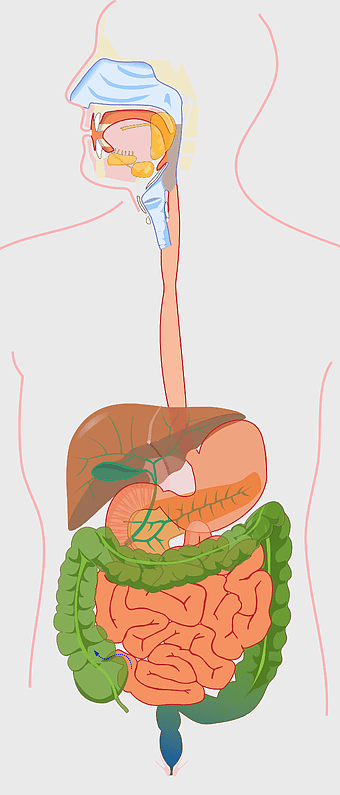

human gastrointestinal tract anatomy, human digestive system illustration, gastrointestinal disease symptoms, human body organ diagram, internal organ visualization, medical anatomy study, digestive health awareness -

Crohn's disease illustration, gastrointestinal tract diagram, large intestine anatomy, digestive system cartoon, medical illustration, human anatomy study, chronic inflammatory bowel condition -

human digestive system, gastrointestinal tract anatomy, liver function, stomach and intestines, digestive health, internal organs diagram, human body systems -

Gastrointestinal tract anatomy, Stomach health, Crohn's disease symptoms, Digestive system, Intestinal inflammation, Human anatomy illustration, Medical diagram -

digestive system diagram, gastrointestinal tract chart, human anatomy illustration, small intestine function, digestive process visualization, internal organ layout, metabolic system overview -

human digestive system illustration, gastrointestinal tract diagram, human body organ system, labeled digestive system, digestive anatomy chart, human internal organs, alimentary canal visualization -

Gastrointestinal tract diagram, Small intestine anatomy, Large intestine function, Apparato digerente illustration, Digestive system structure, Intestinal health, Human anatomy organs -

Gastrointestinal tract illustration, leaky gut syndrome symptoms, small intestine diagram, large intestine function, digestive system health, human anatomy chart, internal organ visualization -